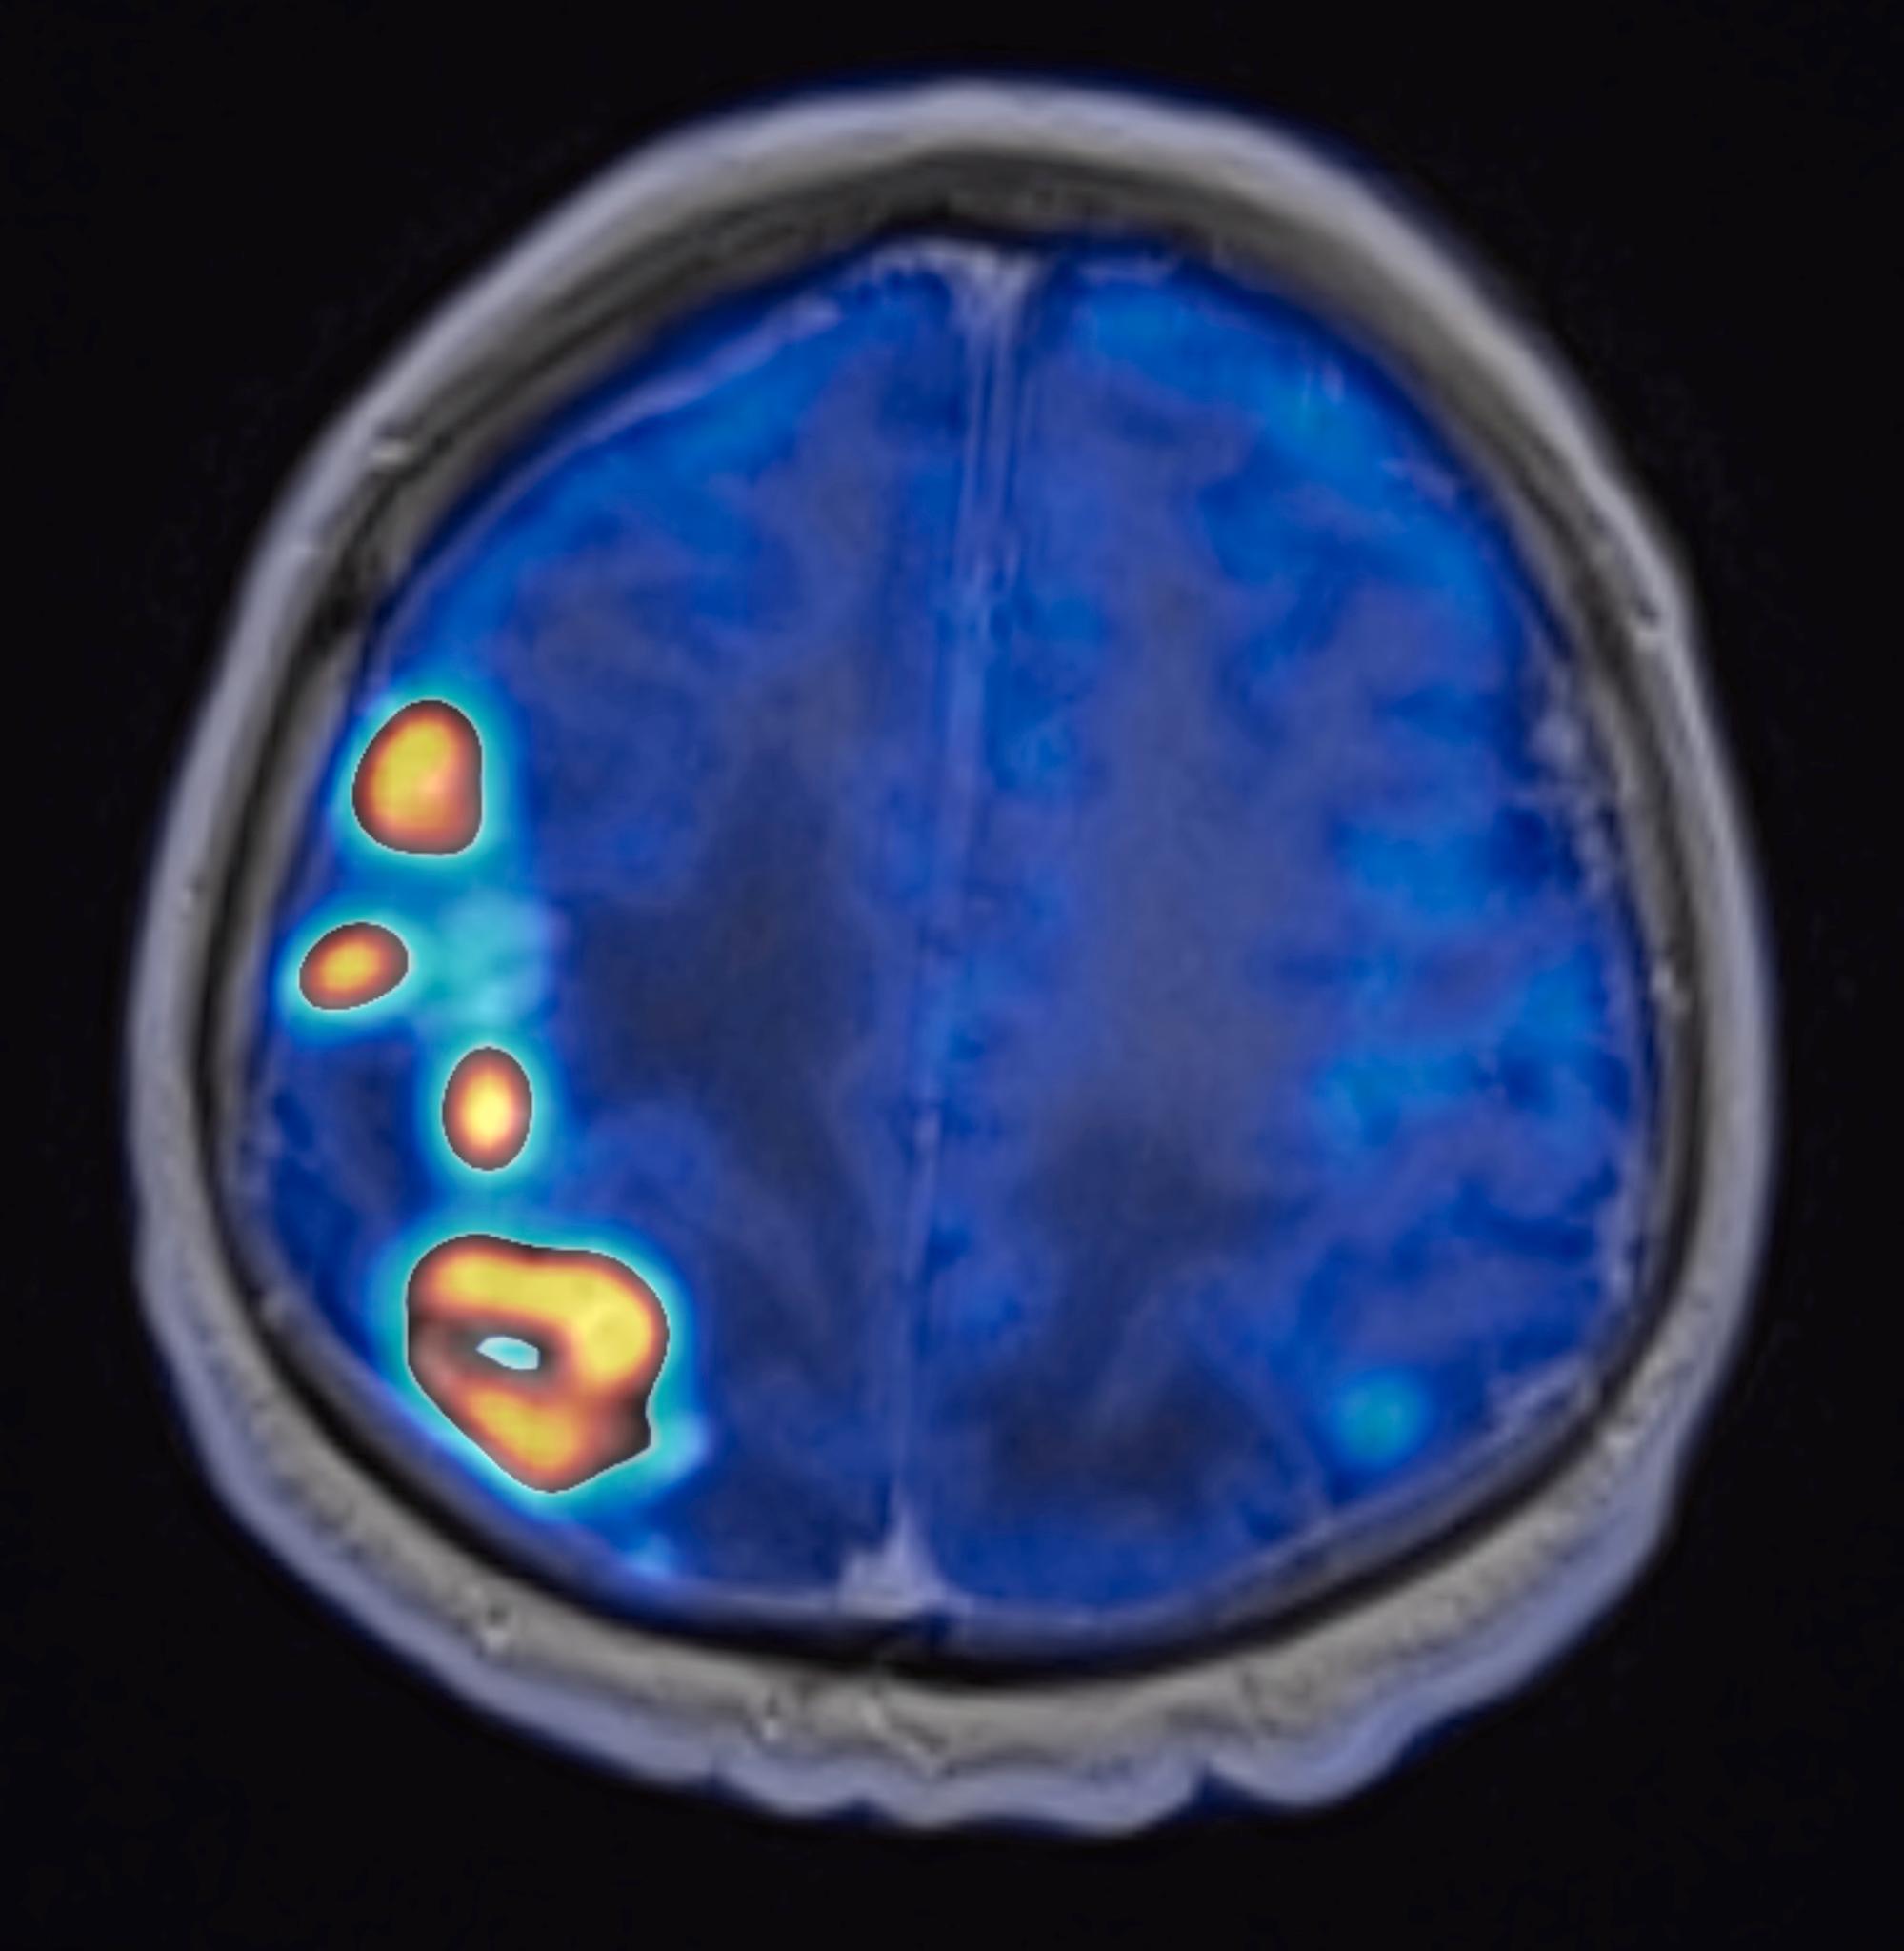

Utilidad clínica de la PET/RM 3T en neuro oncología

Los objetivos de la plática serán: conocer la utilidad de la PET-RM para el diagnóstico de tumores gliales y sus diferenciales, la caracterización de acuerdo a su grado (alto vs bajo grado) y la evaluación de respuesta terapéutica (progresión vs pseudo-progresión) en los tumores cerebrales por medio de radiotrazadores (LAT) y secuencias avanzadas de resonancia magnética 3T.